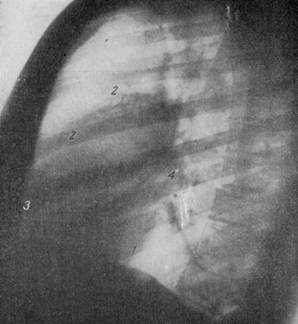

РЕНТГЕНОГРАММА НОРМАЛЬНОЙ ГРУДНОЙ КЛЕТКИ В ПЕРВОМ КОСОМ ПОЛОЖЕНИИ.

1 - дуга левого желудочка; 2 — аорта; 3 — дуга правого предсердия; 4 — дуга левого предсердия; 5 — дуга артериального конуса.